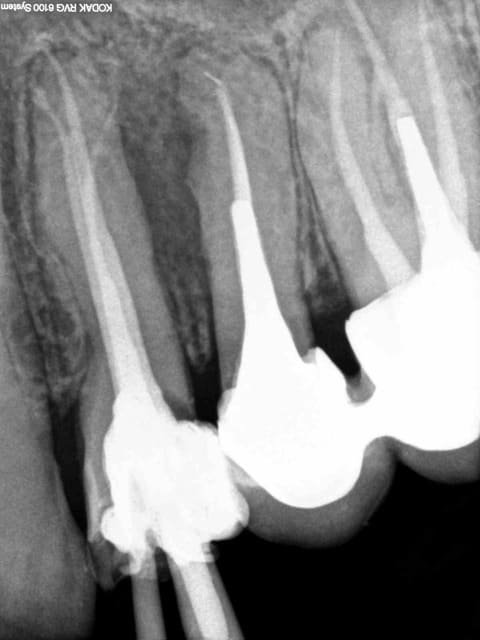

20/12/2014 à 13h11

in vivo 3 ans à l'air libre, monocone scellé, pas de digue : il y a une pèche à l'apex ? non.

6 pvl628 - Eugenol

8 h9nynj - Eugenol